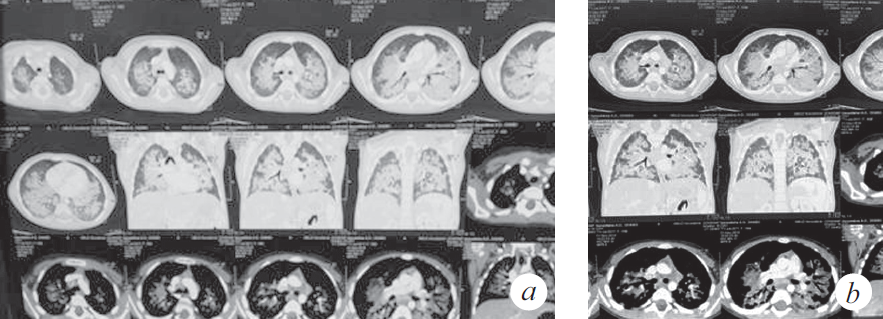

Продуктивный кашель с затрудненной эвакуацией мокроты впервые появился 12.12.2018, нарастала дыхательная недостаточность (одышка, кислородная зависимость), клинически и рентгенологически диагностирован спонтанный пневмоторакс справа (купирован дренированием). Во время дренирования развилась депрессия сердечной деятельности с переходом брадикардии в асистолию, с восстановлением ритма в течение 1 мин. после однократного введения адреналина и закрытого массажа сердца (15 с). Ребенок был переведен на искусственную вентиляцию легких (ИВЛ) (респиратор Savina, Dräger, Германия), отмечалась потребность в FiO2 0,6 для поддержания SpO2 92–95 %. Параметры вентиляции: SIMV, MV 6–7 мл/кг, PIP от 20 до 22 мбар; PEEP (режим BiPAP): минимум 4 мбар, максимум 8 мбар. На следующий день выполнена нижняя трахеотомия и установлена трахеостомическая канюля. Пациентка находилась на ИВЛ 2 мес. со стабильными показателями вентиляции, достигнутое снижение уровня респираторной поддержки было незначительным: PIP 16 мбар, FiO2 0,5, PEEP 4–6 мбар. Динамика газов венозной крови положительная: РО2 50–64 мм рт. ст., SvO2 74–82 %. Динамика КТ представлена на рис. 3–6. В целом томографические изображения характеризовались стабильностью, отличия связаны с эпизодами госпитальной пневмонии: зафиксировано 5 клинически ярких рецидивов. Конец второго месяца заболевания осложнился развитием диарейного синдрома клебсиеллезной этиологии, что заставило редуцировать объем питания на неделю. С декабря до марта отмечен отрицательный баланс по массе тела (минимальный показатель массы тела 8050 г).

Рис. 3. Компьютерная томография органов грудной клетки (через 8 нед. от дебюта заболевания) (a). Сохраняются КТ-признаки паренхиматозного поражения легочной ткани, отмечена положительная динамика в виде уменьшения плотности легочной консолидации (b)

Fig. 3. CT of the chest organs (8 weeks after the onset of the disease) (a). CT-signs of parenchymal lesion of the lung tissue are preserved, positive dynamics in the form of a decrease in the density of pulmonary consolidation are noted (b)

Рис. 4. Компьютерная томография органов грудной клетки (через 11 нед. от дебюта заболевания) (a). КТ-признаки преимущественно базального паренхиматозного поражения легочной ткани, появление выпота в правой плевральной полости (b)

Fig. 4. CT of the chest organs (11 weeks after the onset of the disease) (a). CT signs of a predominantly basal parenchymal lesion of the lung tissue, the appearance of effusion in the right pleural cavity (b)

Рис. 5. Компьютерная томография органов грудной клетки (через 4 мес. от дебюта заболевания) (a). КТ-признаки диффузного субтотального поражения легочной ткани с зонами консолидации в базальных отделах S2, S6, S10 справа и S6 слева, вероятно воспалительного характера (b)

Fig. 5. CT of the chest organs (4 months after the onset of the disease) (a). CT signs of diffuse subtotal lesion of the lung tissue with areas of consolidation in the basal sections S2, S6, S10 on the right and S6 on the left, probably of an inflammatory nature (b)

Рис. 6. Компьютерная томография органов грудной клетки (через 5 мес. от дебюта заболевания) (a). КТ-признаки интерстициального поражения легочной ткани с увеличением площади консолидации в медиальных отделах обоих легких с сохранением в базальных отделах S2, S6, S10 справа и S6 слева (b)

Fig. 6. CT of the chest organs (5 months after the onset of the disease) (a). CT signs of interstitial damage to the lung tissue with an increase in the area of consolidation in the medial sections of both lungs, while maintaining in the basal sections S2, S6, S10 on the right and S6 on the left (b)